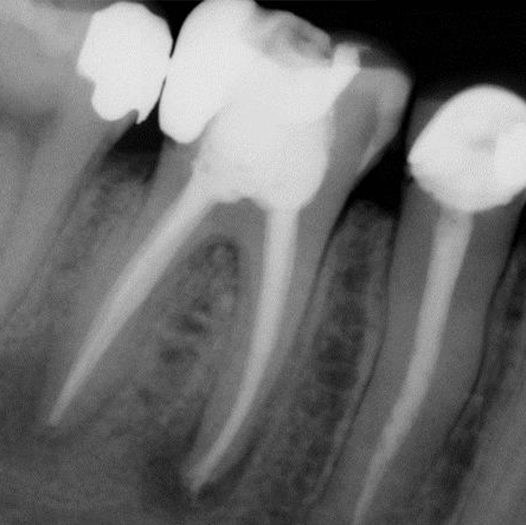

Before

After Root Canal treatment